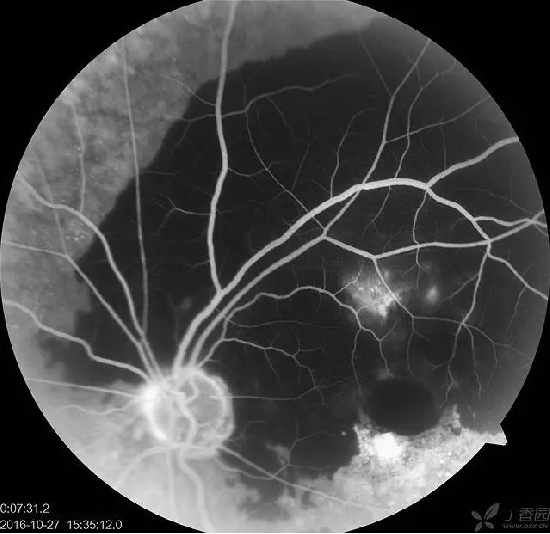

患者,女,74岁。左眼视物模糊3个月。高血压病史。。查体:VOD 0.6 VOS HM 右眼黄斑玻璃膜疣,左眼大片网膜下出血,造影晚期可见荧光渗漏。还是考虑老黄。当时动员她打针,拒绝。半年后复查,变成瘢痕了,照相是小瞳孔下拍的,所以不全。